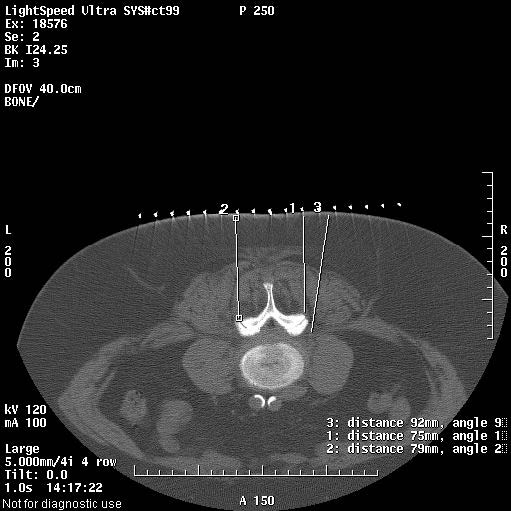

Durch die körperliche Untersuchung sowie der angefertigten Röntgenaufnahmen und Kernspintomographiebilder ist das Ausmaß sowie der genaue Ort Ihrer Wirbelsäulenerkrankung genau bekannt. Im Computertomogramm (CT) des mit unserer Praxis kooperierenden Radiologen wird das betroffene Wirbelsäulensegment mit der befallenen Nervenwurzel und den veränderten kleinen Wirbelgelenken (Facetten) eingestellt. Nun wird in Bauchlage eine kleine lokale Haut-und Stichkanalbetäubung durchgeführt.

Anschließend wird die eigentliche Behandlungsnadel im genau vorgeplanten Winkel, in der richtigen Höhe der Wirbelsäule millimetergenau bis an Nervenwurzel und das Wirbelgelenk vorgeschoben. Dies ist nahezu schmerzfrei – man spürt „einen Druck“ im Rücken. Das anschließend angefertigte Kontroll-CT-Schnittbild zeigt eine korrekte Lage der Behandlungsnadel. Erst jetzt wird das Medikament exakt positioniert.